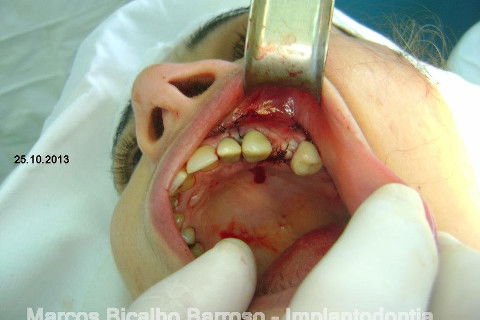

A minha intenção era levantamento de seio e enxerto na vestibular do 24 em única sessão, mas a pedido da paciente, resolveremos o caso por etapas, consideramos a prioridade da resolução desta região dos pré molares e fizemos esta cirurgia de hoje, usando osso autógeno coletado da região da tuberosidade e próximo do alvéolo do 27. Usamos também osso bovino liofilizado Bonefill (Bionnovation) granulação média, e tela de titânio Surgitime (Bionnovation). Não foi possível a instalação do implante em conjunto com o enxerto por considerarmos rebordo extremamente atrófico na espessura (menos de 2 mm na crista e menos de 3 mm até acima do terço médio).

Agradeço aos amigos Jorge Marcos Fernandes e Heddie Ricci por nos proporcionar esta possibilidade de experimentar um material muito bom, tenho usado o Bonefill há bastante tempo com ótimos resultados e agora experimentei a tela de titânio, gostei muito, uma maleabilidade na medida certa, facilidade para cortar e adequar o formato para proporcionar um arcabouço favorável para o enxerto.